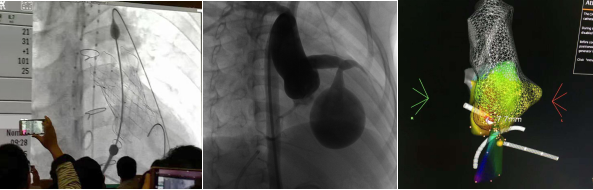

心儿科是国内领先的儿童心脏病临床诊治及科研中心,具有较强的解决疑难病及危重病的技术、设备与科研能力,在诊治各种儿童心脏病方面临床收治病例数量以及治疗效果等多项临床诊疗技术指标、技术水平居国内领先地位,部分项目达到国际先进水平。是卫生部首批先天性心脏病介入治疗培训基地、先天性心脏病介入治疗广东省质量控制单位、广东省“十二五”重点学科及广东省人民医院重点专科。现每年进行儿童心血管疾病介入治疗的病例数超过1000例,多年居全国单中心前三,治疗技术水平居全国领先,世界先进水平。先后吸引了美国、巴西、法国、印度、菲律宾、越南、加纳、香港等国家和地区专家及北京、上海、武汉、长沙、成都等著名医学院校附属医院的医生前来参观及进修学习。

图6 心儿科专科特色技术